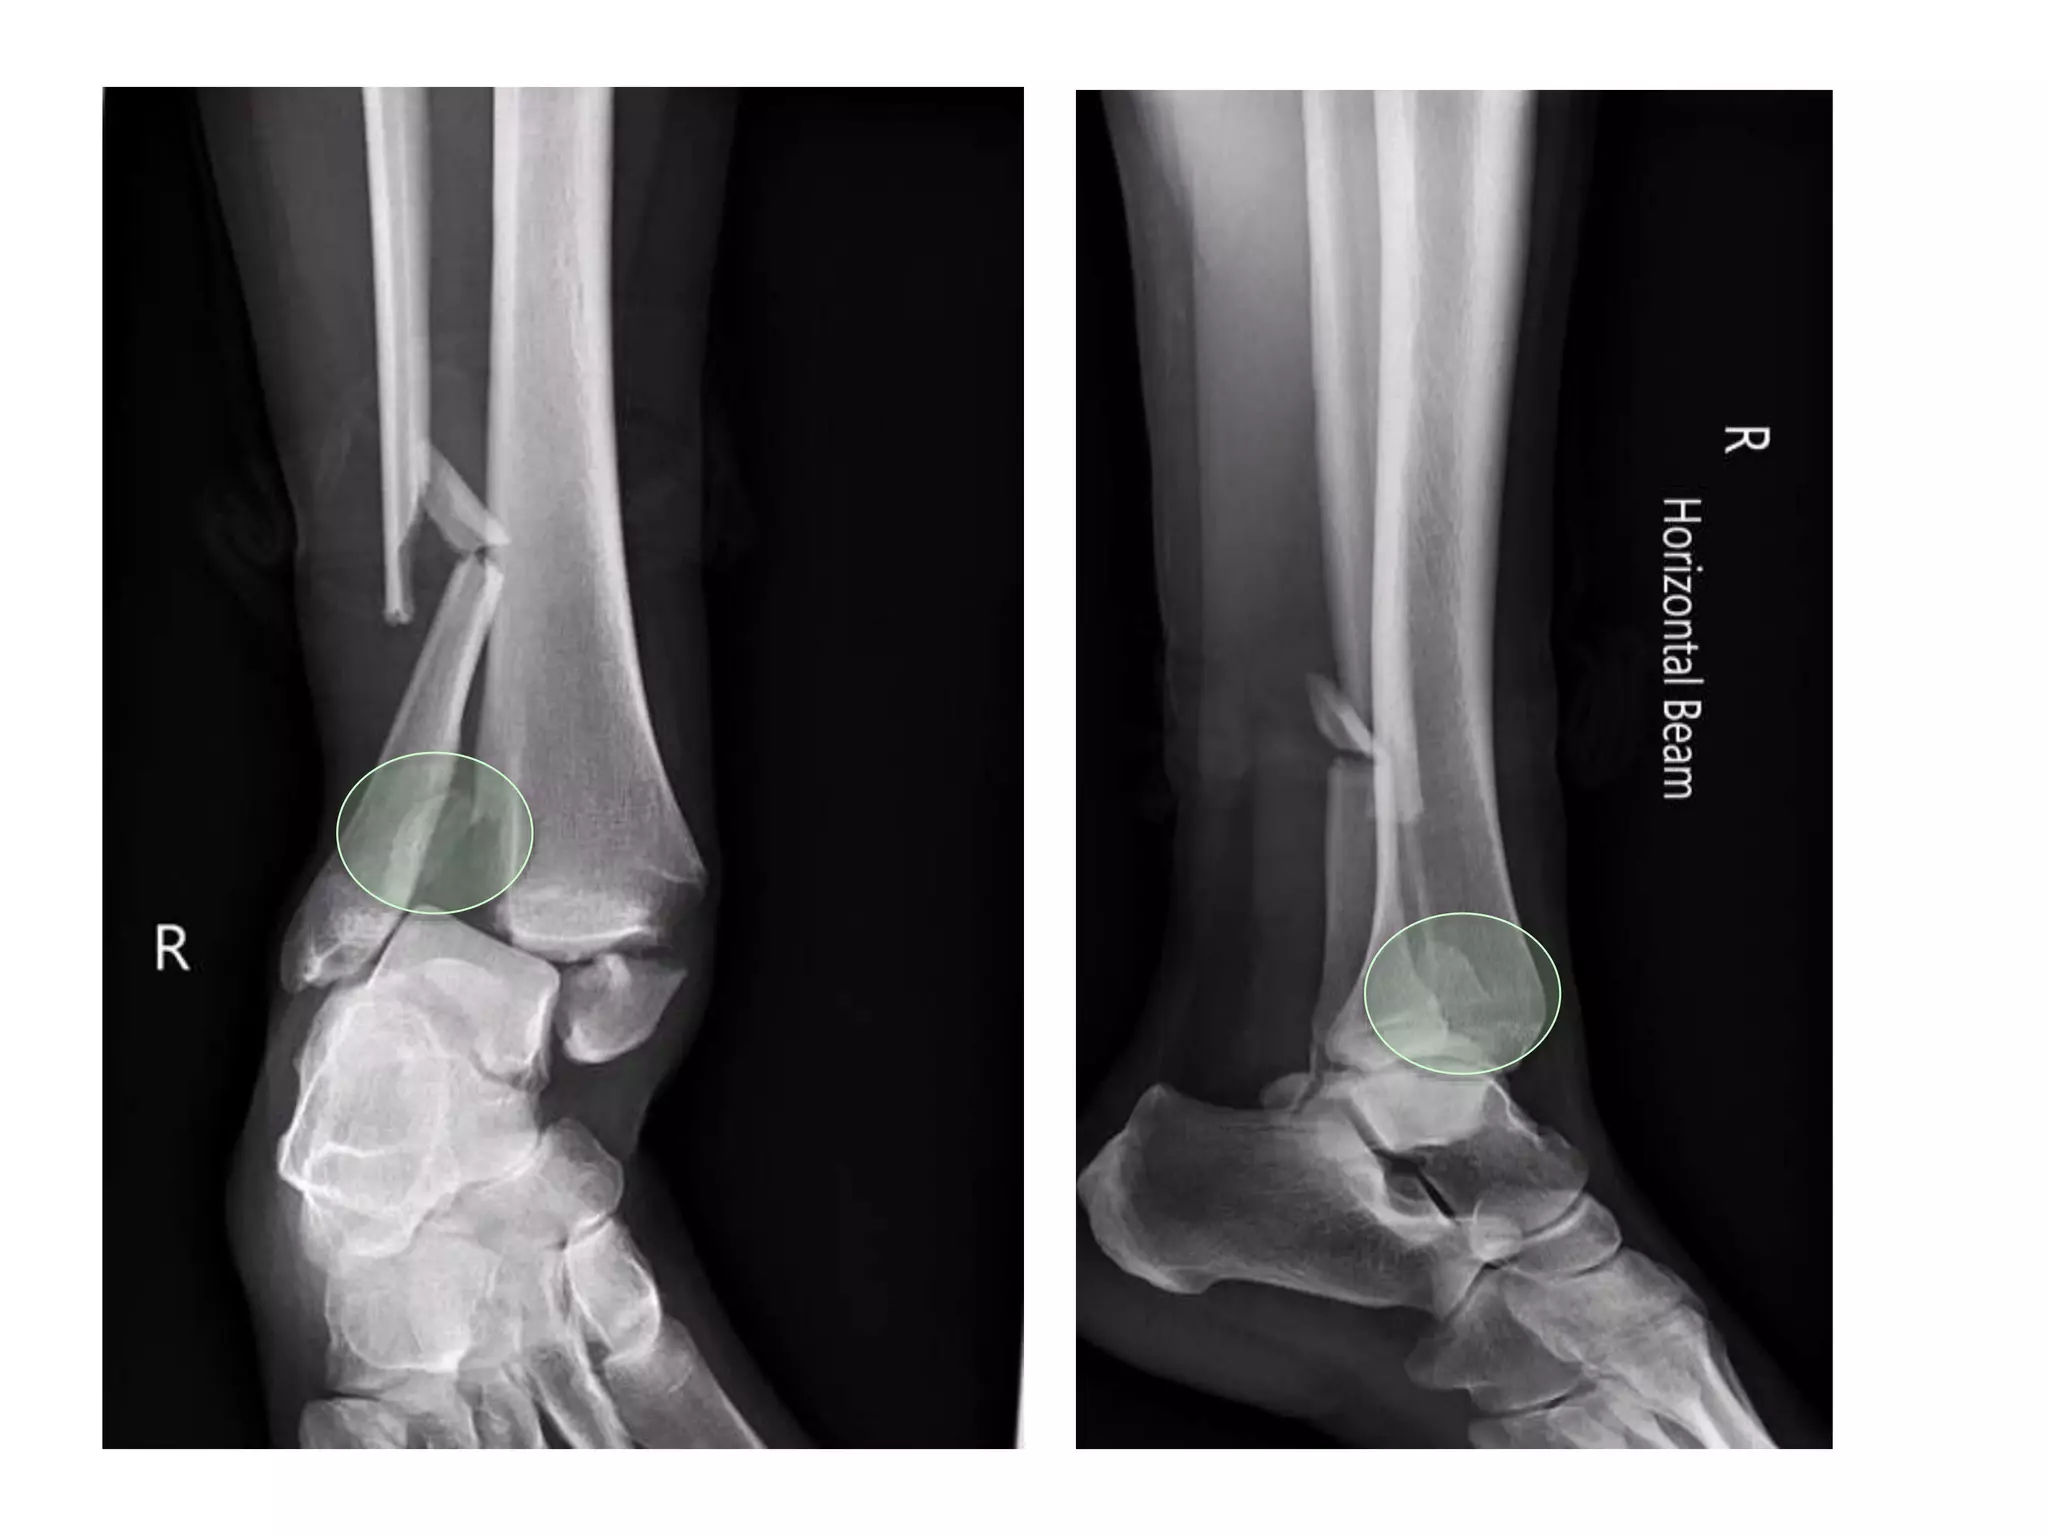

Fracture Dislocation

• Principles in Management

– Early reduction and stabilisation

– Cast / ex-fix or ORIF if swelling appropriate

(usually <6hours or >6 days)